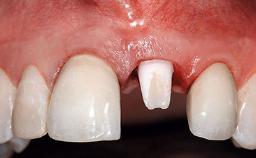

A 32-year-old female Caucasian patient with a compromised maxillary right central incisor was referred to us by a general dentist. Her chief complaints were discomfort and mobility of tooth 11 with unsatisfactory esthetics due to discoloration. The patient reported a previous trauma, some years earlier, as the origin of pathology on the afflicted tooth. Anamnesis was negative for any other dental or periodontal pathology in the remaining dentition. The patient did not take any medication and reported to be a light smoker (5–10 cigs/day). She had high esthetic expectations of her treatment. The extraoral examination revealed a high smile line with full exposure of her maxillary teeth and surrounding soft tissue in the area between the second premolars.

Prosthesis Type FDP

Defining Characteristics One missing tooth to be replaced by an implant-borne crown

Loading Protocol Conventional or early